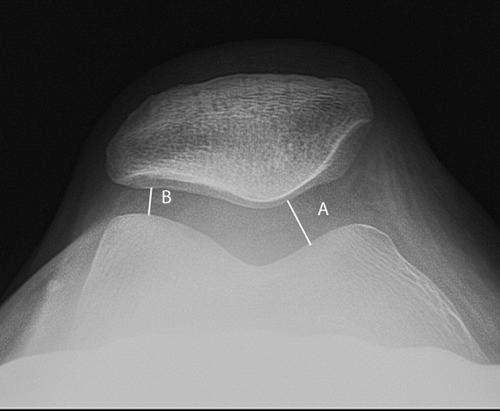

Although disorders of the patellofemoral joint are common in the athlete, their management can be challenging and require a thorough physical examination and radiologic evaluation, including advanced magnetic resonance imaging techniques.

Physical examination and imaging evaluation including standard radiographs are crucial in identifying evidence of malalignment or instability. Magnetic resonance imaging provides valuable information about concomitant soft tissue injuries to the medial stabilizers as well as injuries to the articular cartilage, including chondral shears and osteochondral fractures. Quantitative magnetic resonance imaging assessing the ultrastructure of cartilage has shown high correlation with histology and may be useful for timing surgery.

Evaluation of patellofemoral disorders is complex and requires a comprehensive assessment. Recent advancements in imaging have made possible a more precise evaluation of the individual anatomy of the patient, addressing issues of malalignment, instability, and underlying cartilage damage.